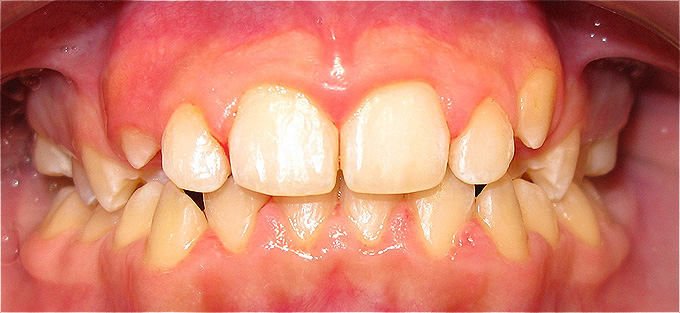

Apinhamento dentário com os dentes caninos em desoclusão (classe II, divisão 2).

![]() |

Após dois anos de tratamento ortodôntico.